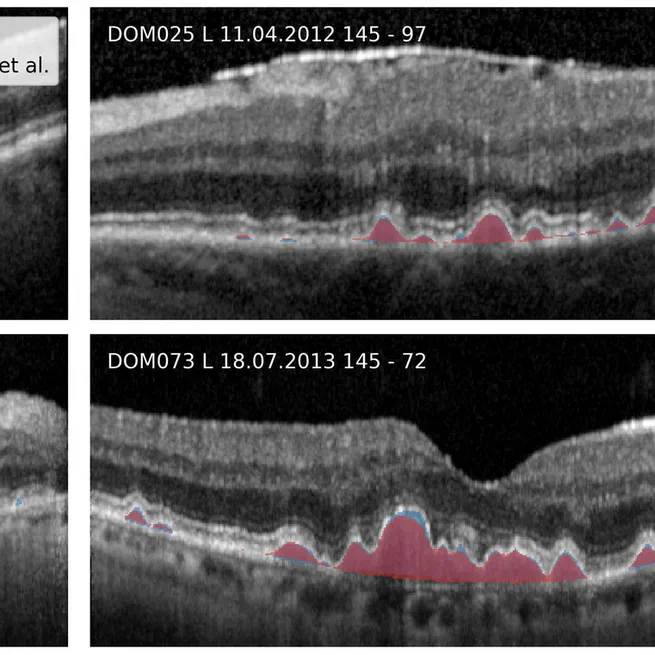

Dockerized CLI for OCT layer segmentation and drusen quantification